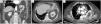

Mujer de 80 años con antecedente de colecistectomía consultó por dolor en fosa ilíaca derecha. La exploración evidenció peritonismo en mesogastrio y la analítica mostró elevación de reactantes. Se practicó una tomografía donde se apreció un engrosamiento intestinal segmentario en el contexto de una probable ileítis, una hernia diafragmática de Bochdalek (HDB) que contenía el riñón izquierdo (fig. 1A), y derrame pleural con atelectasia subyacente del lóbulo inferior izquierdo (figs. 1B y 1C).